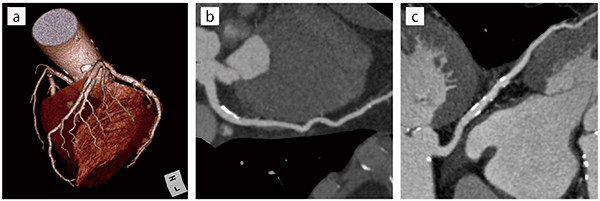

開院前には採算性が不安視された80列CTだったが、開業後のCT検査は1日平均で3〜5件、多い日には10件以上になり、採算ラインとされた検査件数を大きく上回っている。検査としては、胸腹部、頭頸部に加えドック受診者も増えており、全身CTや肺がんドックでのCT撮影も増加している。齋藤名誉院長は、「高精細な画像で、冠動脈の石灰化から副鼻腔炎(図2)まで診断できています。必要な時に他院へ依頼せずに,すぐに撮影して結果を患者さんに説明できるメリットを実感しています」と述べる。

■Aquilion Lightning/Helios Editionによる臨床画像

図2 副鼻腔炎

上気道炎症状にて来院された患者で見つかることが多い。